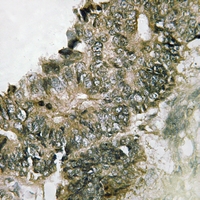

Immunohistochemical analysis of RSK1 (Phospho-S380) staining in human colon cancer formalin fixed paraffin embedded tissue section. The section was pre-treated using heat mediated antigen retrieval with sodium citrate buffer (pH 6.0). The section was then incubated with the antibody at room temperature and detected using an HRP conjugated compact polymer system. DAB was used as the chromogen. The section was then counterstained with haematoxylin and mounted with DPX.